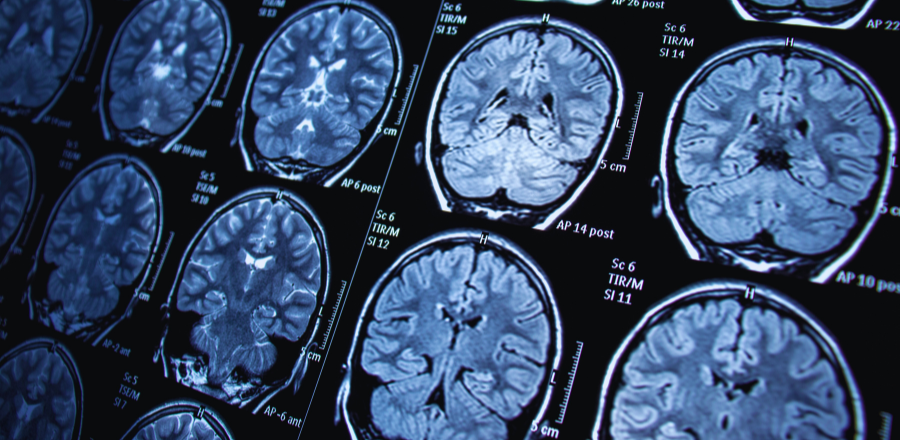

Diagnostic imaging is not a simple transactional service; it is a critical component of comprehensive care that requires clinical reasoning, interpretation, and integration into a patient-centred management plan. For this reason, radiologist-led oversight of imaging protocols, interpretation, and reporting must remain central.